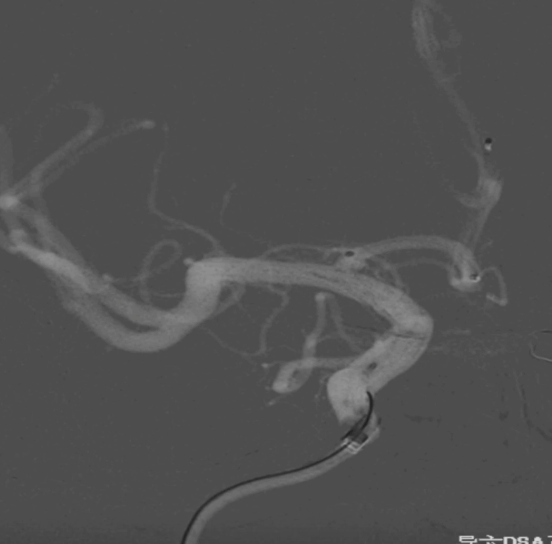

工作位正位造影(图片)

工作位正位造影(视频)

术前外院 DSA 2025-02

箭头所指右侧A1微小动脉瘤